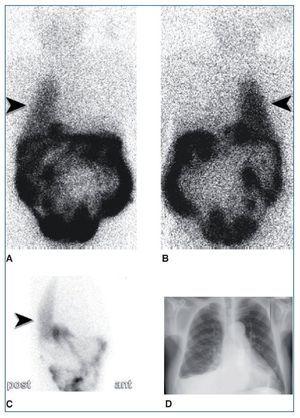

Para la realización de la prueba se administraron 2 mCi de 99mTc-MAA (macroagregados de albúmina) a través del catéter de diálisis, con posterior infusión de 2 l de solución de DP. A los 90 min se adquirieron imágenes planares de tórax y abdomen en decúbito supino en proyecciones anterior, posterior y laterales, con equipo Gammacámara Sopha®, colimador de baja energía y alta resolución, 330 kc por imagen en matriz de 128 × 128. En las imágenes se objetivó actividad del radiotrazador en la práctica totalidad del hemitórax derecho, demostrándose así la existencia de CPP (fig. 1).

Figura 1. Gammagrafía planar de tórax y abdomen con 99mTc-MAA. Actividad del radiotrazador en hemitórax derecho (punta de flecha). A) Proyección anterior. B) Proyección posterior. C) Proyección lateral derecha. D) Radiografía de tórax posteroanterior: leve derrame pleural derecho.